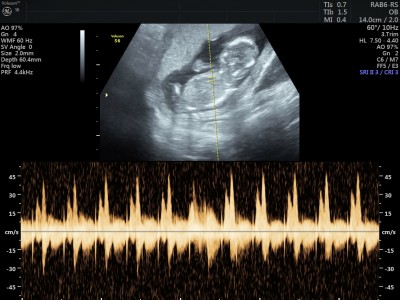

Kızlaaar keseye bakarak cinsiyet yorumlayanlar vardı acaba bana da yorum yaparmısınız

Cinsiyet biliyormusunuz bana erkek gibi geldi ama rabbim saglicakla alsin bende hamileyim.kizim var 12 haftaliktq hamileyim bilmiyorum ne cikicak oglum.olsun istiyorum raabim ikisinide tattirri ins

Bende sizin gibi erkek hissettim birden :)) hiç öyle hissedebilen biride değilim oysaki. İki kızım var üçüncüye gebeyim sağlıklı Salih bir oğlum olsun istiyorum. İnsaAllah Rabbim bizlere o meyveyide tattirir